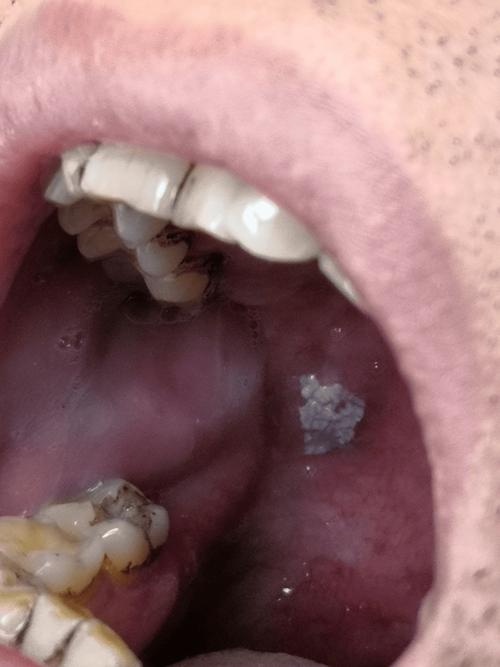

口腔内壁发白不痛不痒是何原因? 下面我为您详细分析一下可能的原因,以及应该如何应对。(图片来源网络,侵删) 最常见且通常无害的原因 这些情况是良性的,一般不需要特殊治疗,您不必过于担心。 角化异常 / 角化不良 这是最常见的原因之一,口腔黏膜的某些区域(特别是颊黏膜、牙龈)会因为长期摩擦、刺激而发生生理性的增厚和角化,外观上看起来...